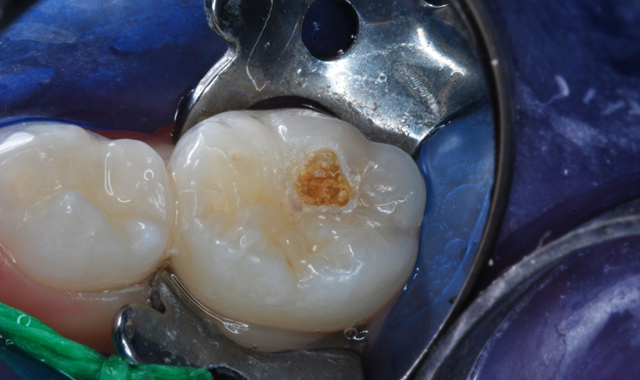

Fig. 3 Fig. 4

After appropriate local anesthesia, the tooth was isolated with a rubber dam, using the “slit dam” method (Fig. 2). Outline form was prepared using a high-speed diamond bur, exposing the extent of the caries lesion (Fig. 3). Carious dentin was debrided with slow-speed round burs and the cavity preparation was completed (Figs. 4 and 5).